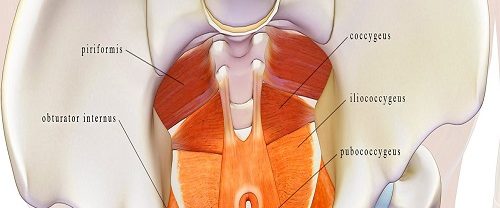

Ürojinekoloji Nedir? Ürojinekoloji, üroloji ve jinekoloji disiplinlerinin birleşiminden oluşan bir tıp dalıdır. Bu alan, kadın üreme sistemi ve idrar yollarıyla ilgili sağlık sorunlarını inceleyen ve tedavi eden bir uzmanlık alanıdır. Kadın anatomisi gereği idrar yolları ve üreme organları birbirine yakın olduğundan, bu alan iki farklı tıp uzmanlığının kesişim noktasında yer alır. Ürojinekolojinin Kapsamı Ürojinekoloji, kadınların…

TOT Vagynal Syling Operasyonları TOT Vaginal Sıkılaştırma Operasyonları Tanım ve Amacı TOT Vagynal Syling Operasyonları | TOT (Transobturator Tape) vaginanın sıkılaştırılması amacıyla yapılan bir cerrahi işlemdir. Genellikle kadınların yaş aldıkça veya doğum sonrası yaşadığı vajinal sarkma ve inkontinans gibi sorunları çözmek için tercih edilir. Bu operasyon, vajinal kasların ve dokuların zayıfladığı durumlarda vajinanın yeniden sıkılaştırılmasını…

Rektosel Ameliyatı Tanım ve Açıklama Rektosel Ameliyatı, rektumun (kalın bağırsağın son kısmı) vajinaya doğru sarkması durumudur. Bu durumda, rektumun arka duvarı zayıflayarak veya gerilerek vajinaya doğru bir çıkıntı oluşturur. Rektosel genellikle pelvik taban kaslarının zayıflaması veya hasar görmesi sonucunda ortaya çıkar. Rektosel ameliyatı, rektosel tedavisinde en sık kullanılan yöntemlerden biridir. Bu ameliyat, rektoselin düzeltilmesini ve…

İdrar Kaçırma Ameliyatı İdrar kaçırma, idrarın istem dışı olarak mesaneden dışarı sızması durumudur. Bu durum, kişinin günlük yaşamını etkileyen bir sorun olabilir ve yaşam kalitesini olumsuz yönde etkileyebilir. İdrar kaçırma genellikle pelvik taban kaslarının zayıflığı veya kontrolünün kaybı nedeniyle ortaya çıkar. İdrar kaçırma farklı tiplere ayrılabilir. En yaygın üç tür idrar kaçırma şunlardır: Stres İnkontinansı:…